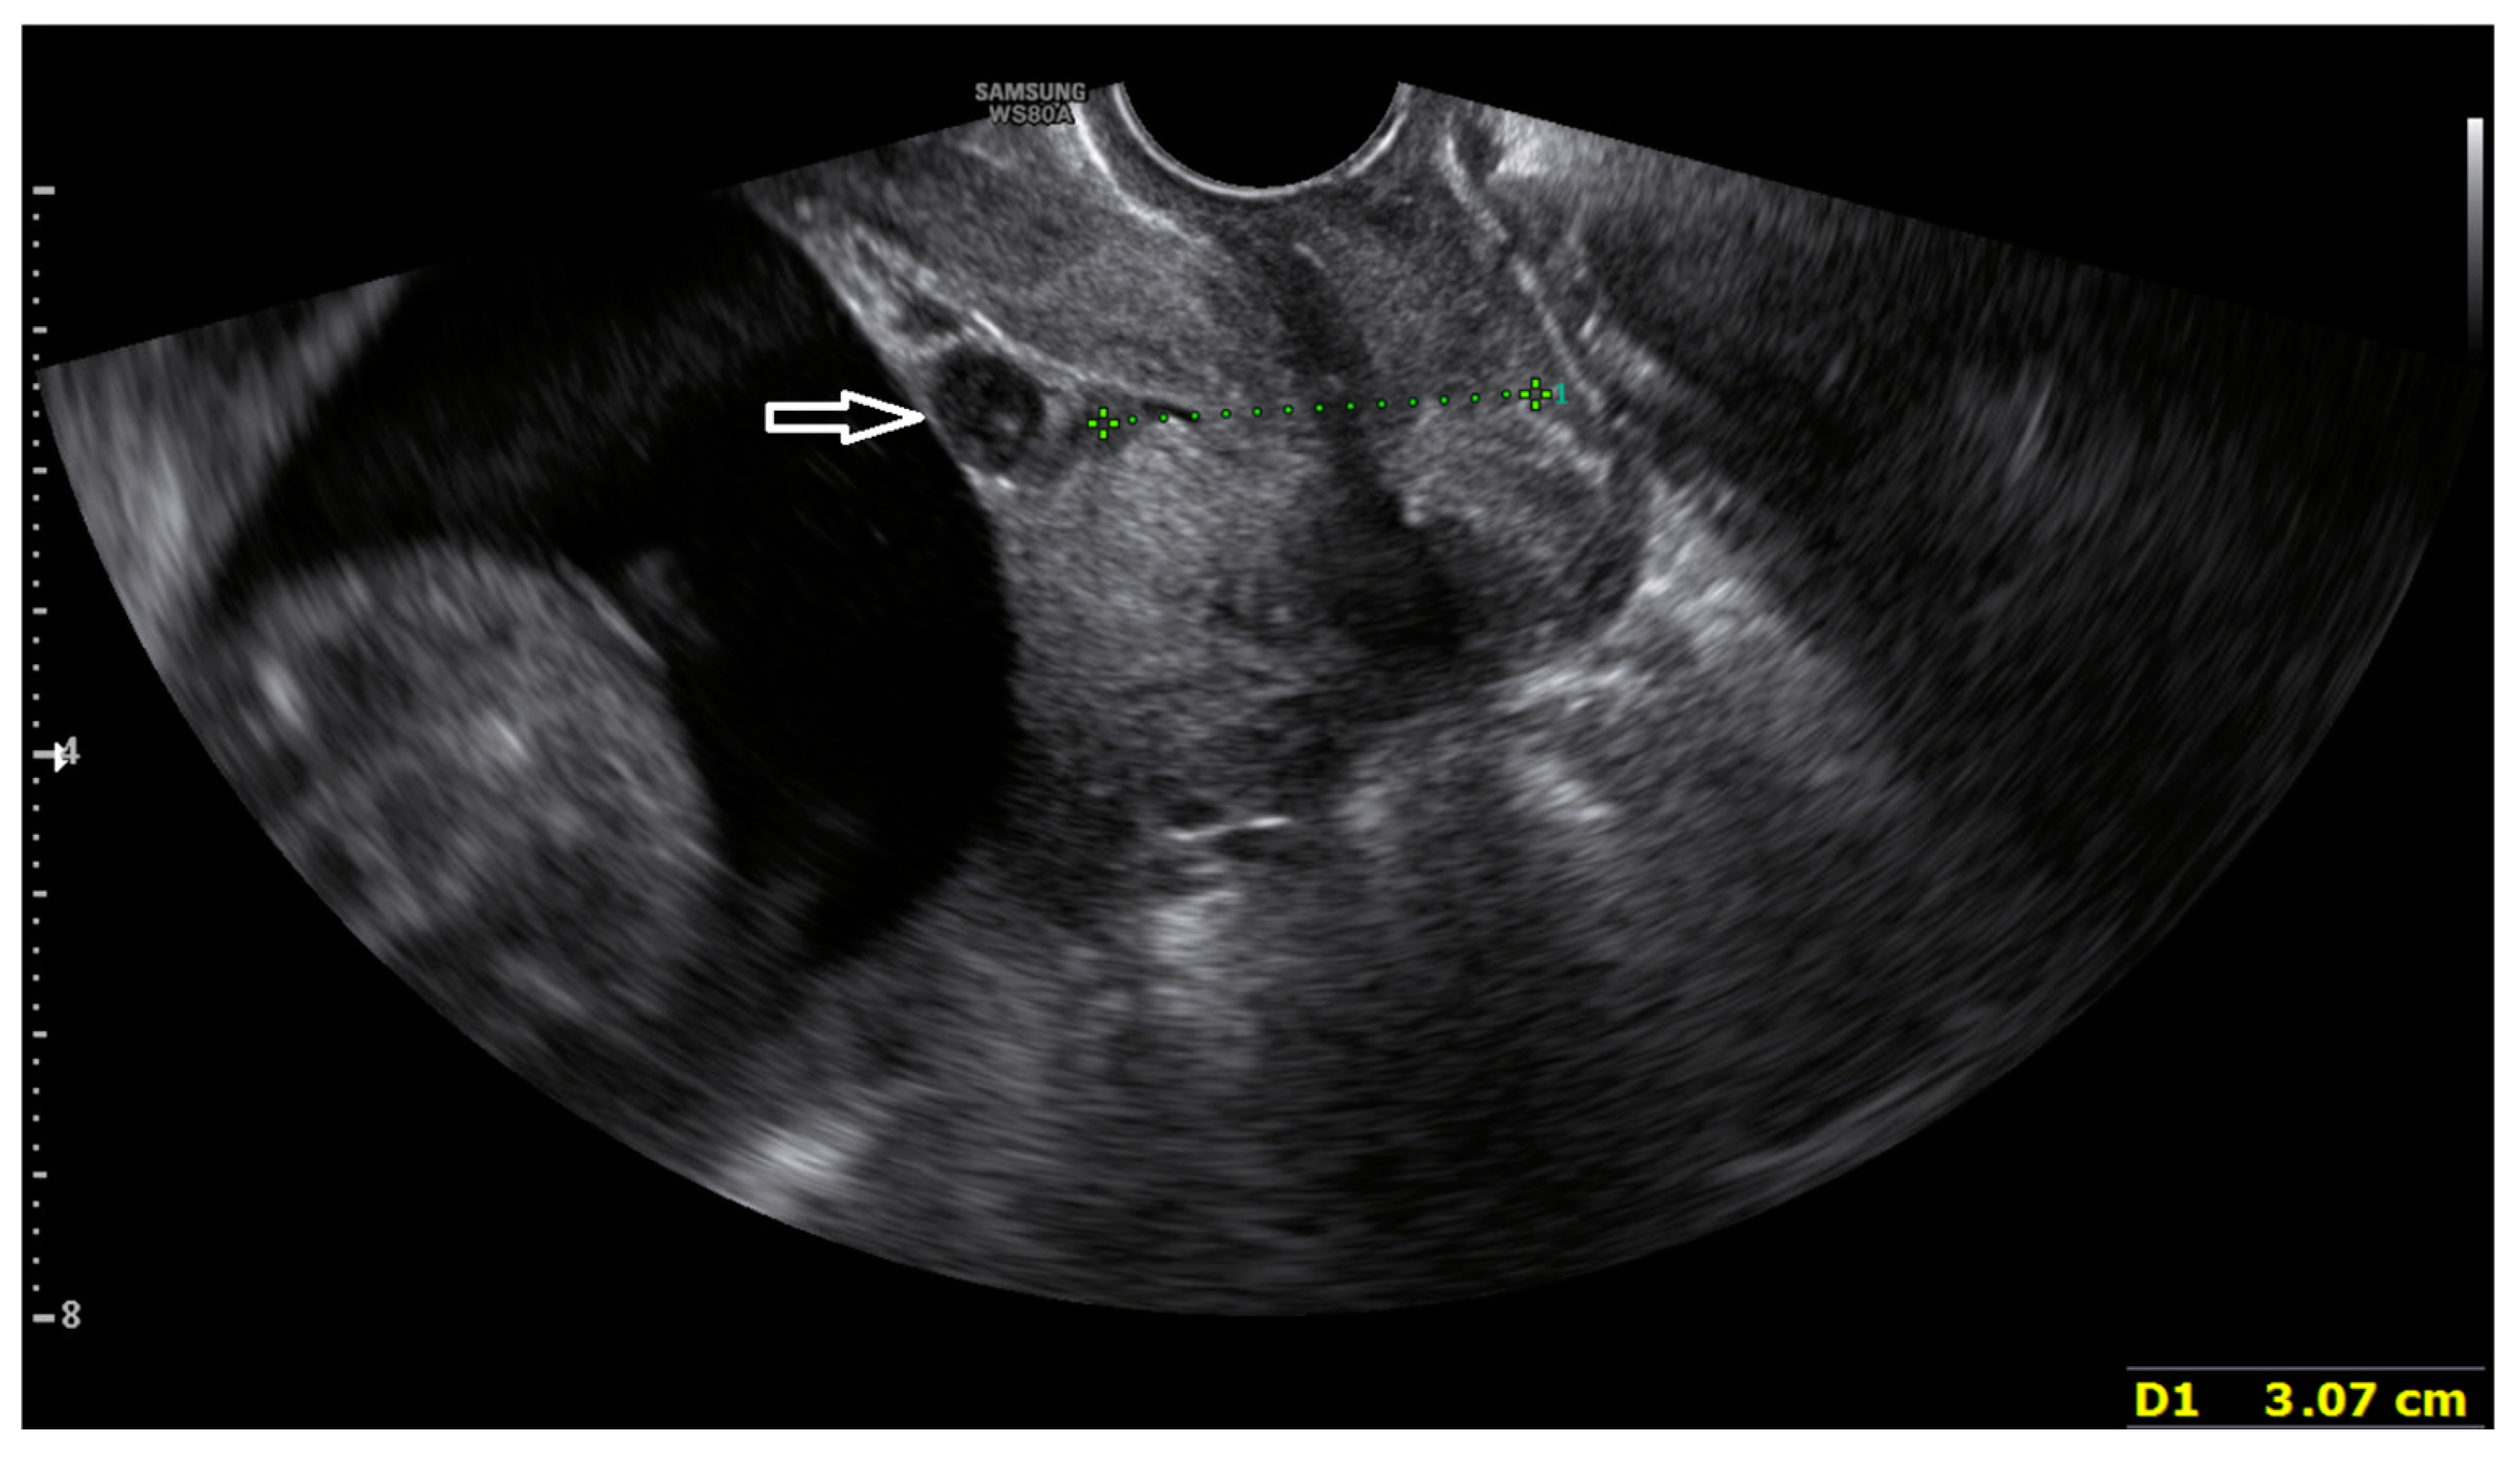

2. Case Report